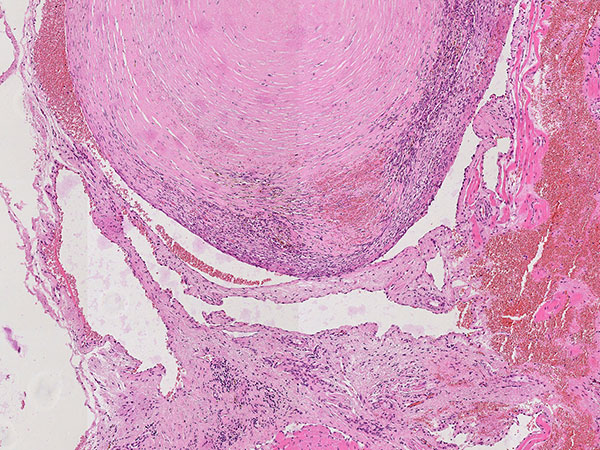

Hämatoxylin-Eosin-Färbung, 64-fache Vergrößerung: Schichtartiger, vor allem zentral vorwiegend bindegewebiger Aufbau des bereits älteren, teilorganisierten Phlebolithen. Umgeben wird der Phlebolith von multiplen vermehrten, irregular aufgebauten, dünnwandigen Gefäßräumen.